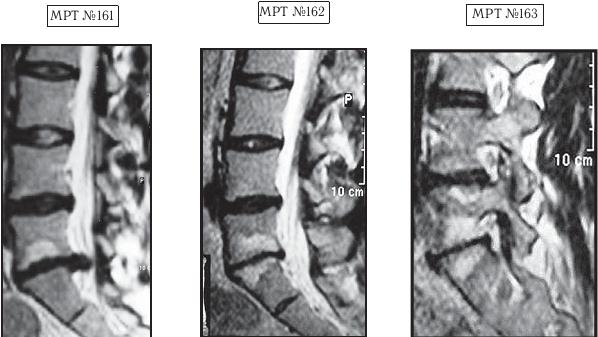

МРТ № 3

На МРТ № 3 — поясничный отдел позвоночника. (На данном «контрольном» снимке наблюдаются остаточные явления дегенеративно-дистрофического процесса в сегменте LV-SI после устранения методом вертеброревитологии секвестрированной грыжи межпозвонкового диска.)

В поясничном отделе форма позвоночного канала, создаваемая телом и дужками позвонка, вариабельна, но чаще она пятиугольная. В норме позвоночный канал в пояснично-крестцовом отделе сужен в переднезаднем диаметре на уровне LIII и LIV позвонков. Его диаметр каудально увеличивается, и поперечное сечение канала приобретает форму, близкую к треугольной, на уровне LV-SI. У женщин канал имеет тенденцию к расширению в нижней части крестцовой области. Сагиттальный диаметр значительно уменьшается от LI к LIII почти неизменен от LIII к LIV и увеличивается от LIV к LV. В норме переднезадний диаметр позвоночного канала в среднем равен 21 мм (15–25 мм).

Существует простая и удобная формула определения ширины позвоночного канала:

нормальный сагиттальный размер не менее 15 мм;

11–15 мм — относительный стеноз;

менее 10 мм — абсолютный стеноз. Уменьшение этого соотношения свидетельствует о сужении канала.

Высота поясничных межпозвонковых дисков 8–12 мм, нарастает от LI до LIV-LV, обычно уменьшается на уровне LV-SI